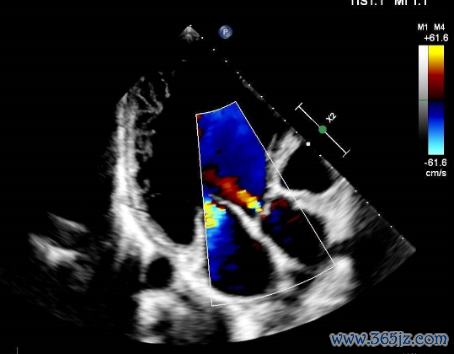

超声心动图:

左心大,左房前后径44mm,左室前后径71mm,右心各房室腔、主动脉及肺动脉内径简单;

心室壁及室远离厚度简单,各节段指令幅度减低,左室侧壁、后壁中段及心尖段肌小梁加多、呈珊瑚状改动,纰缪与室腔重迭,肌层变薄;

二尖瓣中-多量返流,三尖瓣一丝返流,主动脉瓣一丝返流,心功能减低,左心室射血分数(LVEF)30%(图2-5)。

图2 超声心动图效劳

图3 超声心动图效劳

图4 超声心动图效劳

图5 超声心动图效劳